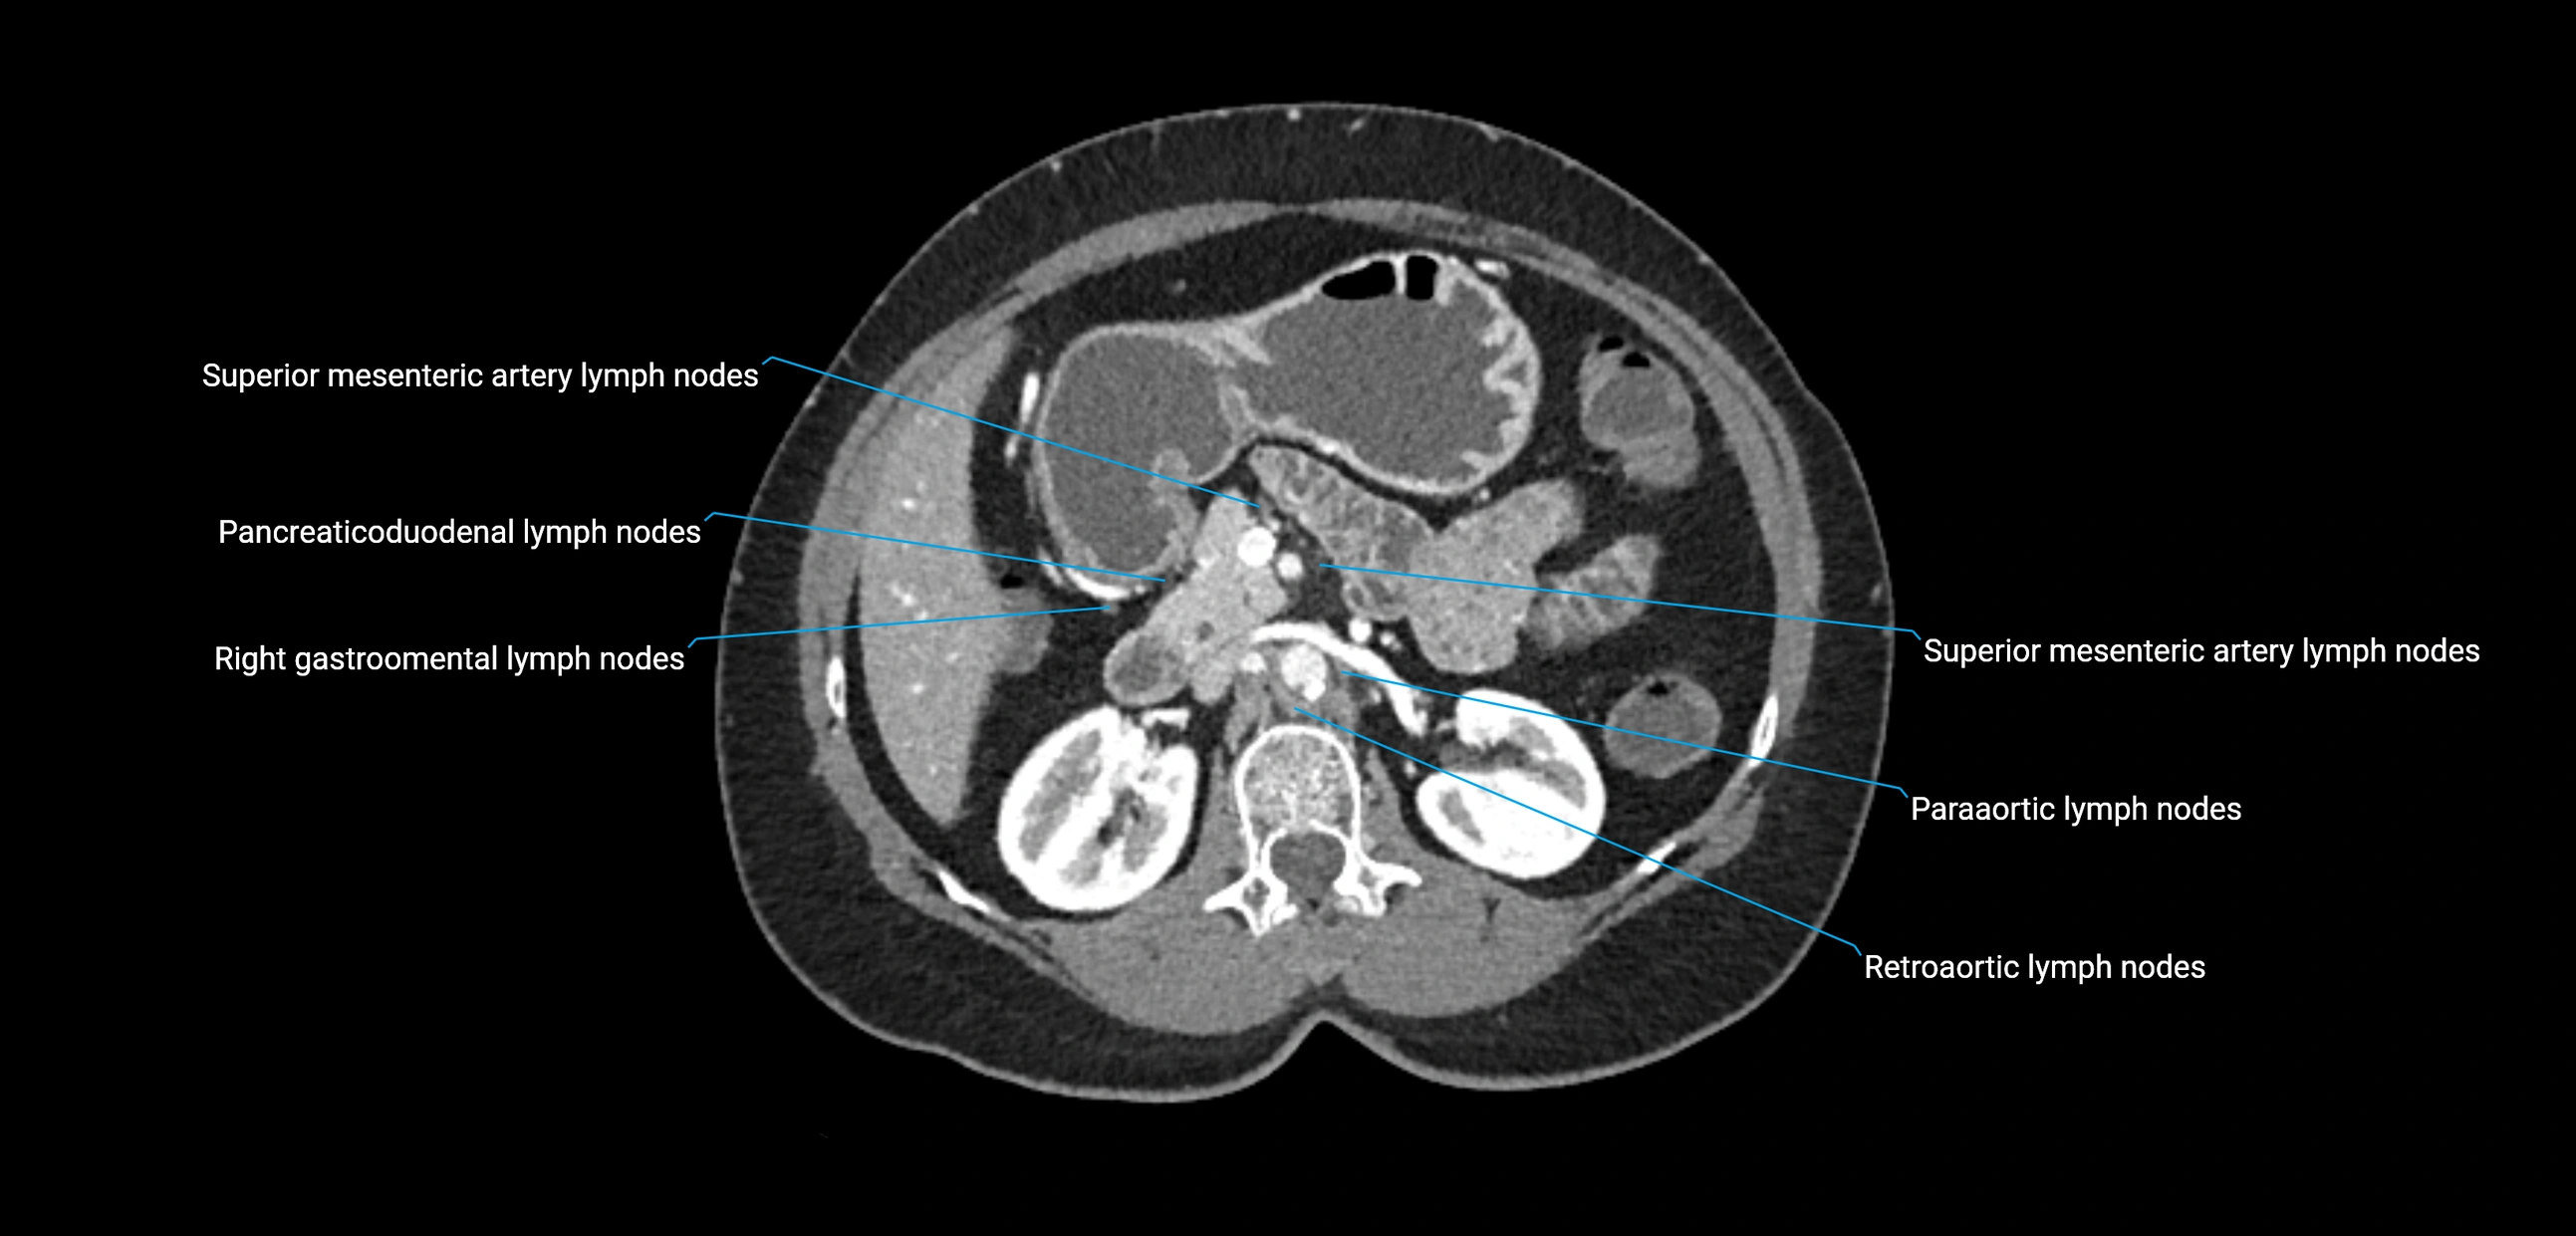

CT image

image